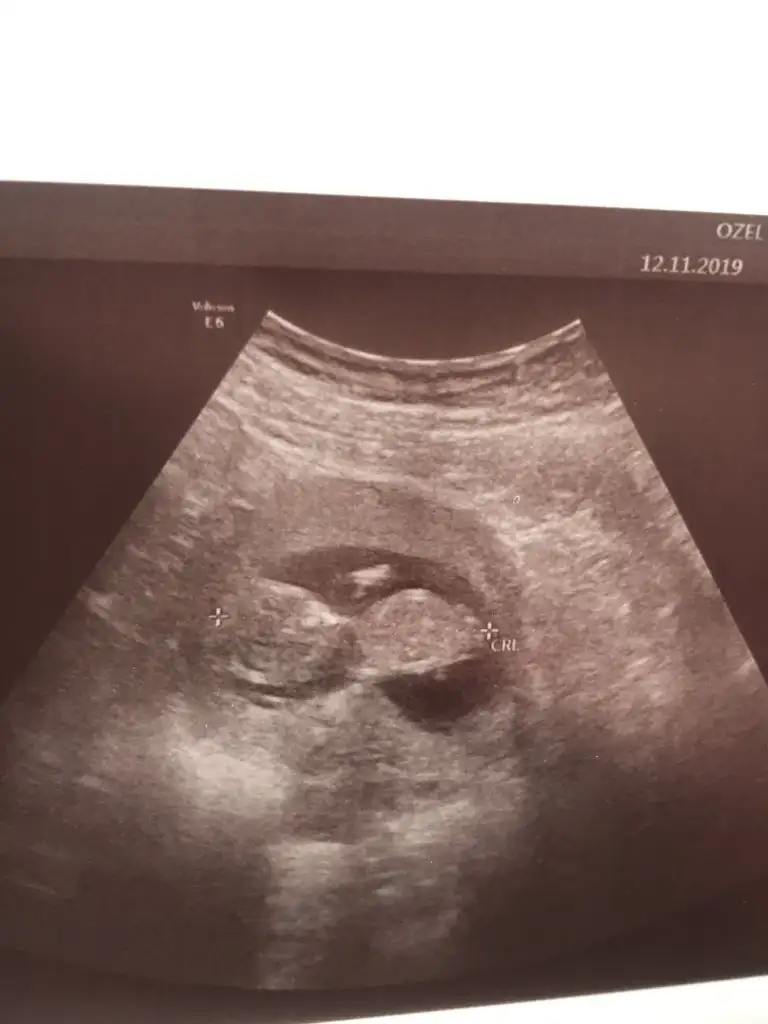

11 yada 12 hafta usg olmalı nub için sanki kız gibi gibi diyorum varsa usg paylaşın

11+4 haftalığız cinsiyet tahmini alabilirmiyiz

doktor kiz dedi ama hani yanilma payi olabiliyorya ben sizin tahminlerinize guveniyorum11 yada 12 hafta usg olmalı nub için sanki kız gibi gibi diyorum varsa usg paylaşın

Kaç haftalık usg net değil nub için 11 yada 12 olmalıNasıl anlıyorsun ben hiç anlayamadım

Kız12.haftadan iki foto

Bu 12+4 , başka usg de var aynı bugün çekilen 12+4 hepsi ama çıkıntı sadece bunda görünüyor.Başka usg varmı 11 yada 12 olmalı